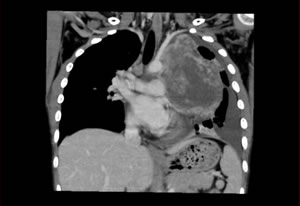

CT画像

CT検査

上の画像のように、被膜をもった胸腺腫では、周囲の臓器への浸潤はありませんが、 胸腺がんでは周囲の血管や気管等、重要な組織に浸潤して増大してしまいます。